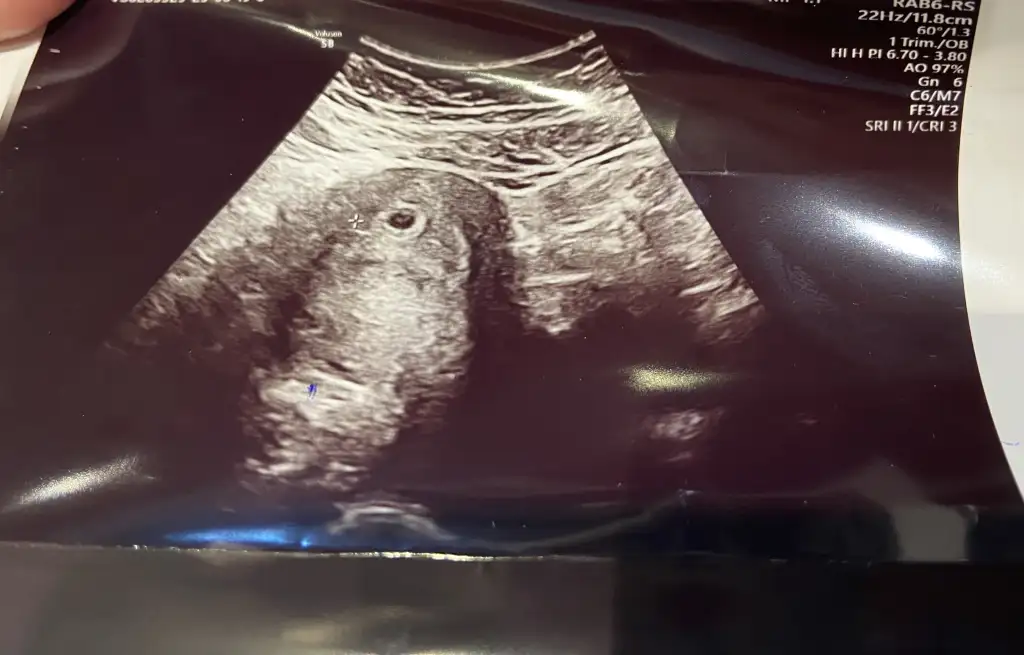

oh çok şükür çok sevindiiimmm allah sağlıkla kucağına almayı nasip etsin bende dün doktordan sonra biraz rahatladım bunlar hep kötü tecrübelerimiz olduğu için oluyor bence hala birilerine haber vermeye korkuyorum aslında çok istesemde ama çok şükür her şey güzel ilerliyo güzel olacak inşallahCanım anneler. Ben dayanamadım acile gittim enfeksiyon şüphesi ile. Önce ebelerle konuştum vajinal muayene ile bakabilirz ıdrar alamayız önce tanı dediler çıktım eşimle konuştum ablamı aradım fln daha önce kimyasal gebelikte vajınal muayene olmustum dr.un hareketleri canımı sıkmıştı ve sonrasında cok kanamam olmstu neyse ablam yüreklendirdi 1 cm sokuyor bsy yok dedi girdim hemen bebişime baktılar Dr kalp atımını açtı. Başta acaba dedim yok ya başka sestir tekrar açtı hocam kalp sesi mi dedim evet dedi. Allah'ıma şükürler olsun 6+5 dedi 6+6 bitmek üzereydi ama zaten 3 gun geç yumurtlama oldugu ıcım tam güzel çıktı yani günü de uyumlu hatta ovulasyon ay göre önde göründü. Nasıl kaygılı nasıl canım sıkkındı yok memem söndü yok öğürmedim yok hapşırmadım. Kaygılarım boşaymış. Lütfen kendinize zulmetmeyin benim gibi. Enfeksiyon için de bol su ıc dedi yanma koku kaşıntım yok diye enfeksiyon cıksa da ben sana 12 hafta asla antibiyotik vermem saglkkcagna da gideblrsn tabi dedi ama o da vermez vermemeli antibiyotik... Batma agrı vs ıcın Progestan verdi. Allah'ıma şükürler olsun sizler de güzel düşünün.![]()

Çok şükür canım ben de şimdi doktordan geldim. Crl 6,5 cm olmuş 6+4 ile uyumlu dedi ama cihaz çok kötüydü karından göremedi kese bayağı büyük ama boş dediNasıl rahatladım bebeğim anlatamam iyi ki varsın canım zaten seninle konuştuktan sonra çok daha iyiydi mm kız Ben ilk defa Progestan kullanacağım fitil olarak al dedi . Günlerdir adam gibi uyumuyorum umarım az da olsa uyku yapar bana Benm şimdi salı günü gitmeme gerek yokmuş kuzum

Canım merak etme gayet güzel ve haftanla uyumlu o minik beyaz şey bebişin işteKızlar merhaba ben de nisan annesi olacağım inşallahAralık ayında kalp atışı alamadığımız için bi kaybım var aşırı korkuyorum yeniden kalp atışı alamazsak diye

Bebiş mi o dersinÇok şükür canım ben de şimdi doktordan geldim. Crl 6,5 cm olmuş 6+4 ile uyumlu dedi ama cihaz çok kötüydü karından göremedi kese bayağı büyük ama boş dediben üzül tabiiii

birde vajinal bakalım dedi bebiş göründü hemen kalp atışınıda duydum geçen hafta görmüştük sadece

Canım merak etme gayet güzel ve haftanla uyumlu o minik beyaz şey bebişin işte

Evet bebişşş pirinç tanesi gibiBebiş mi o dersinayyy inşalalh kalp atışı dıyarım ya